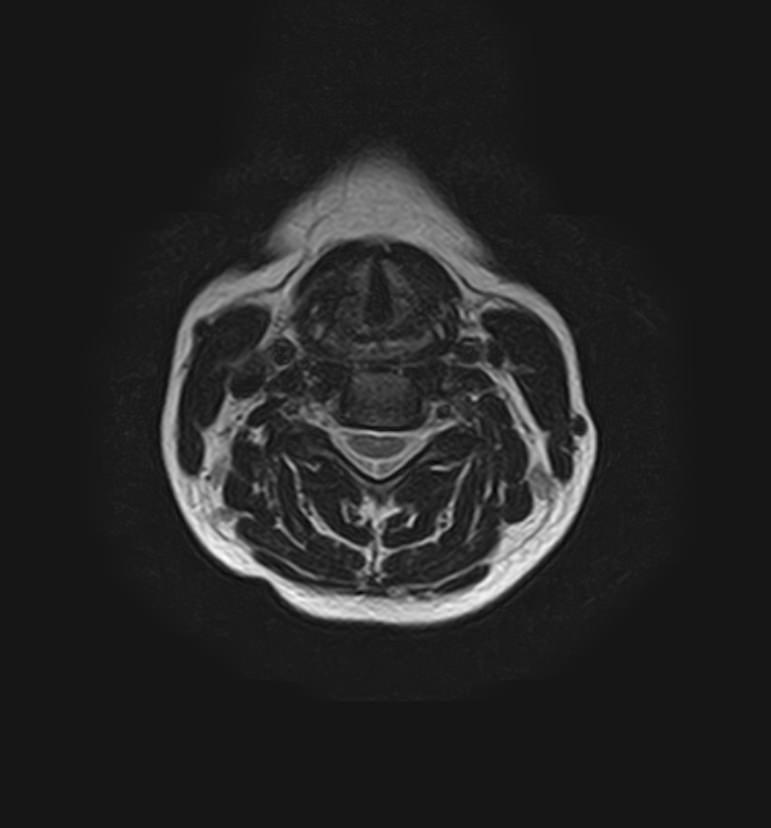

МРТ шейного отдела позвоночника позволяет проводить диагностику дегенеративных заболеваний позвоночного столба (в том числе межпозвонковых грыж, протрузий, остеохондроза), выявлять воспалительные, травматические изменения и объемные образования в области шейных позвонков и спинного мозга.

МРТ шейного отдела позвоночника позволяет выявить практически любые изменения в костных и мягких тканях. Исследование характеризуется высокой результативностью при следующих нарушениях:

• компрессия спинномозговых корешков и спинного мозга;